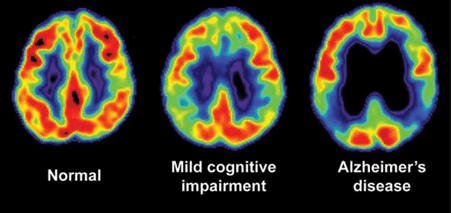

18 F-Fluorodeoxyglucose PET showing variations in Alzheimer and Dementia

Despite this, the individual may experience memory lapses, such as forgetting familiar words or placing everyday objects. The progression to mild cognitive impairment can be predicted by increasing tau protein in CSF, right entorhinal cortex thickness, and right hippocampus volume on MRI.

PET scan indicating changes in brain glucose metabolism (shown in red and yellow). More prominent in AD indicated by brain tissue with diminished metabolic activity.

Patients’ memory or nonmemory areas, such as executive ability or language function, are impaired. The individuals continue to work, socialize, and operate on their own.

Patients with mild cognitive impairment develop dementia at a rate of 10% yearly. According to a national survey, stress is the leading cause of mild cognitive impairment, particularly in individuals under 50.